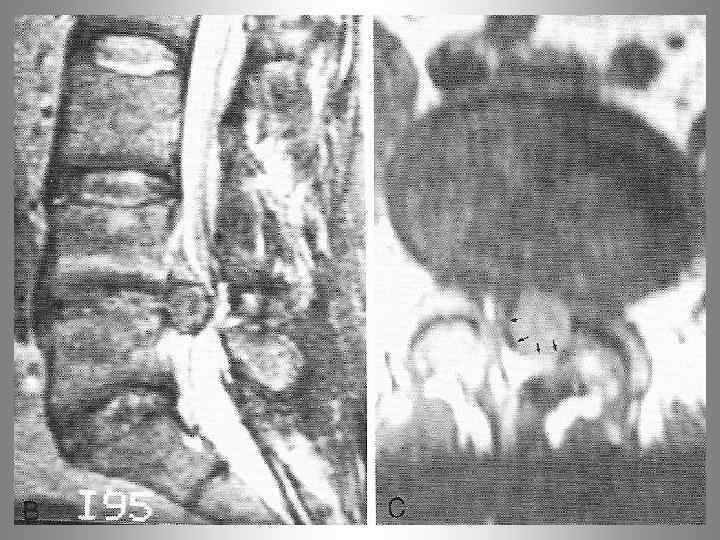

MRT - позвоночника. Спондилит L 2 - L 3 позвонков.